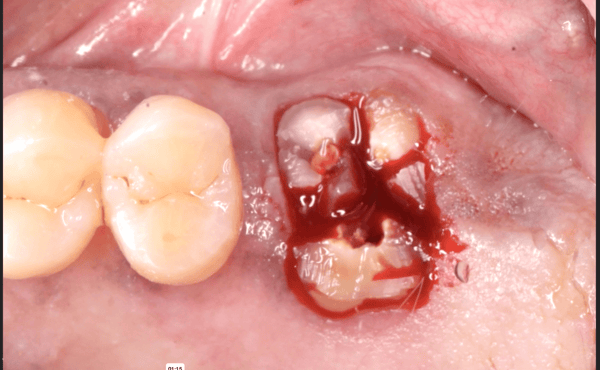

I am feeling really humble. I’ve placed multiple implants and thinking this should be a straightforward case. I was wrong. I know it’s poorly planned and freehand did not go well. Are these restorable? Should I explant and redo? If I do remove these, how easy is it to remove these?